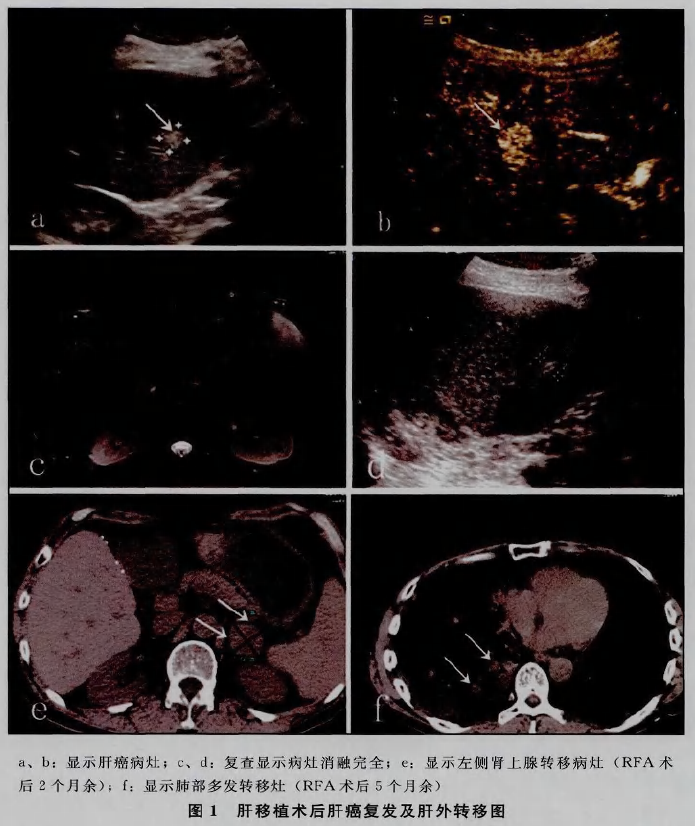

11例患者(均为男性,年龄37~64岁,平均49岁)共行12次肝脏RFA治疗,共消融病灶数19个,术后随访1~11个月。术后局部完全消融率100 (19/19),局部复发率0,肝内复发率66.7 (8/12)。

超声引导下射频消融治疗肝移植术后肝癌的局部灭活率高,并发症较少,安全性较高,可作为肝移植术后肝癌的一项局部治疗手段。但由于免疫抑制剂的应用等原因,肝内及肝外肿瘤的复发率较高,不能有效延缓肿瘤进展,需要联合其他治疗手段。